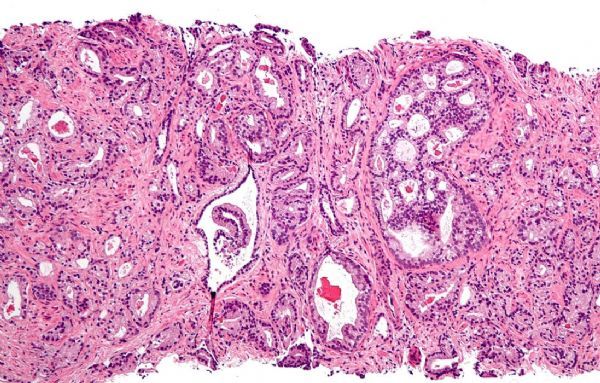

深入解读前列腺癌的新型疗法和筛查手段的进展状况

2018年3月23日 讯 /生物谷BIOON/ --近日,发表在国际杂志the Journal of Clinical Oncology上的研究报告中,来自美国西北大学综合癌症中心的研究人员通过研究描述了恶性前列腺癌疗法的最新研究进展情况,同时研究人员呼吁采用一种平衡的方法来进行疾病的早期诊断

研究者Maha Hussain博士说道,这代表了我一生中很大的一部分工作,在我有生之前获得这些研究成果让我感觉非常激动。前列腺癌是美国男性中最常诊断出的一种癌症类型,其引发的死亡率在所有类型癌症中排名第二。

大部分前列腺癌患者并不会死于前列腺癌,然而转移性去势抵抗性前列腺癌(mCRPC,metastatic castration-resistant prostate cancer)患者的预后往往较差,在这类前列腺癌中,患者机体的癌症常常会扩散到其它部位,尽管患者采用了激素疗法但病情仍然会发生进展。目前很多科学家非常感兴趣开发治疗前列腺癌患者的新型治疗手段,而该领域就是研究者Hussain非常感兴趣的一个研究领域。